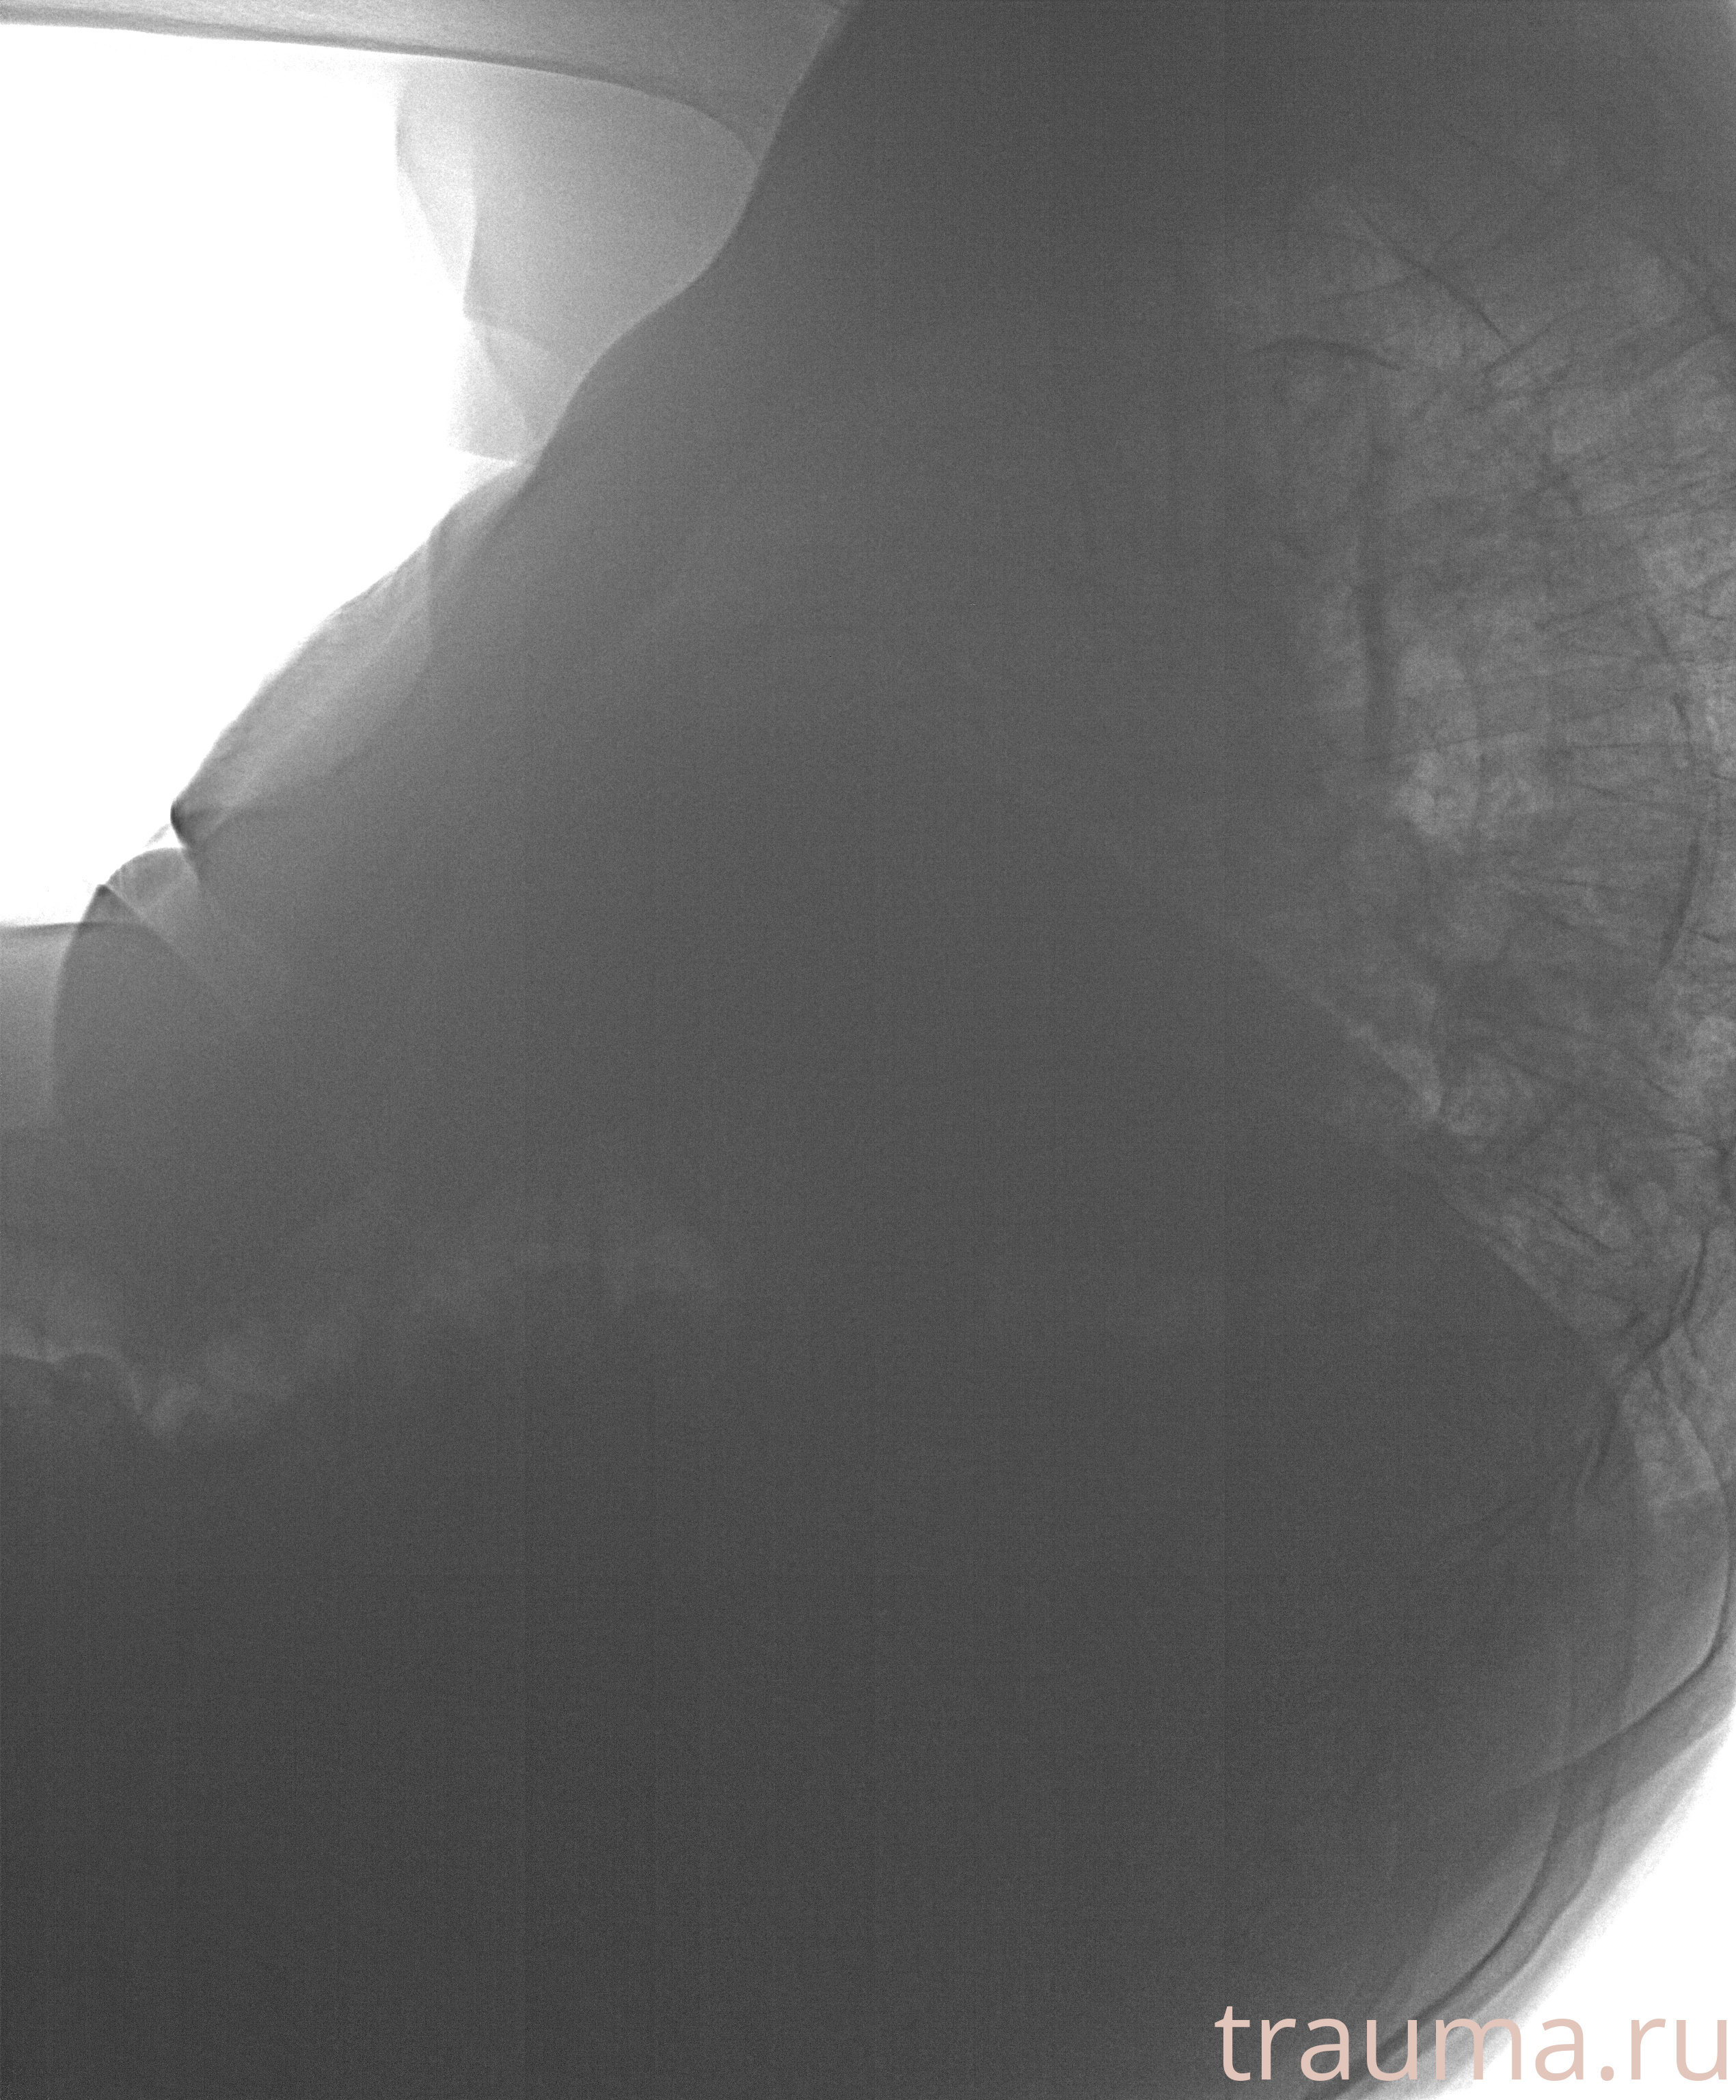

Рентген на дому: по вашему адресу приезжает врач-рентгенолог, травматолог-ортопед с мобильным рентгеновским аппаратом, проводит диагностику травмы или заболевания, делает необходимые рентгенограммы, дает рекомендации по дальнейшему лечению. Получить качественные снимки в домашних условиях возможно благодаря уникальной методике, разработанной МосРентген Центром для института  Склифосовского